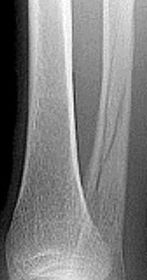

| What do the arrows indicate? | Infectious periostitis |